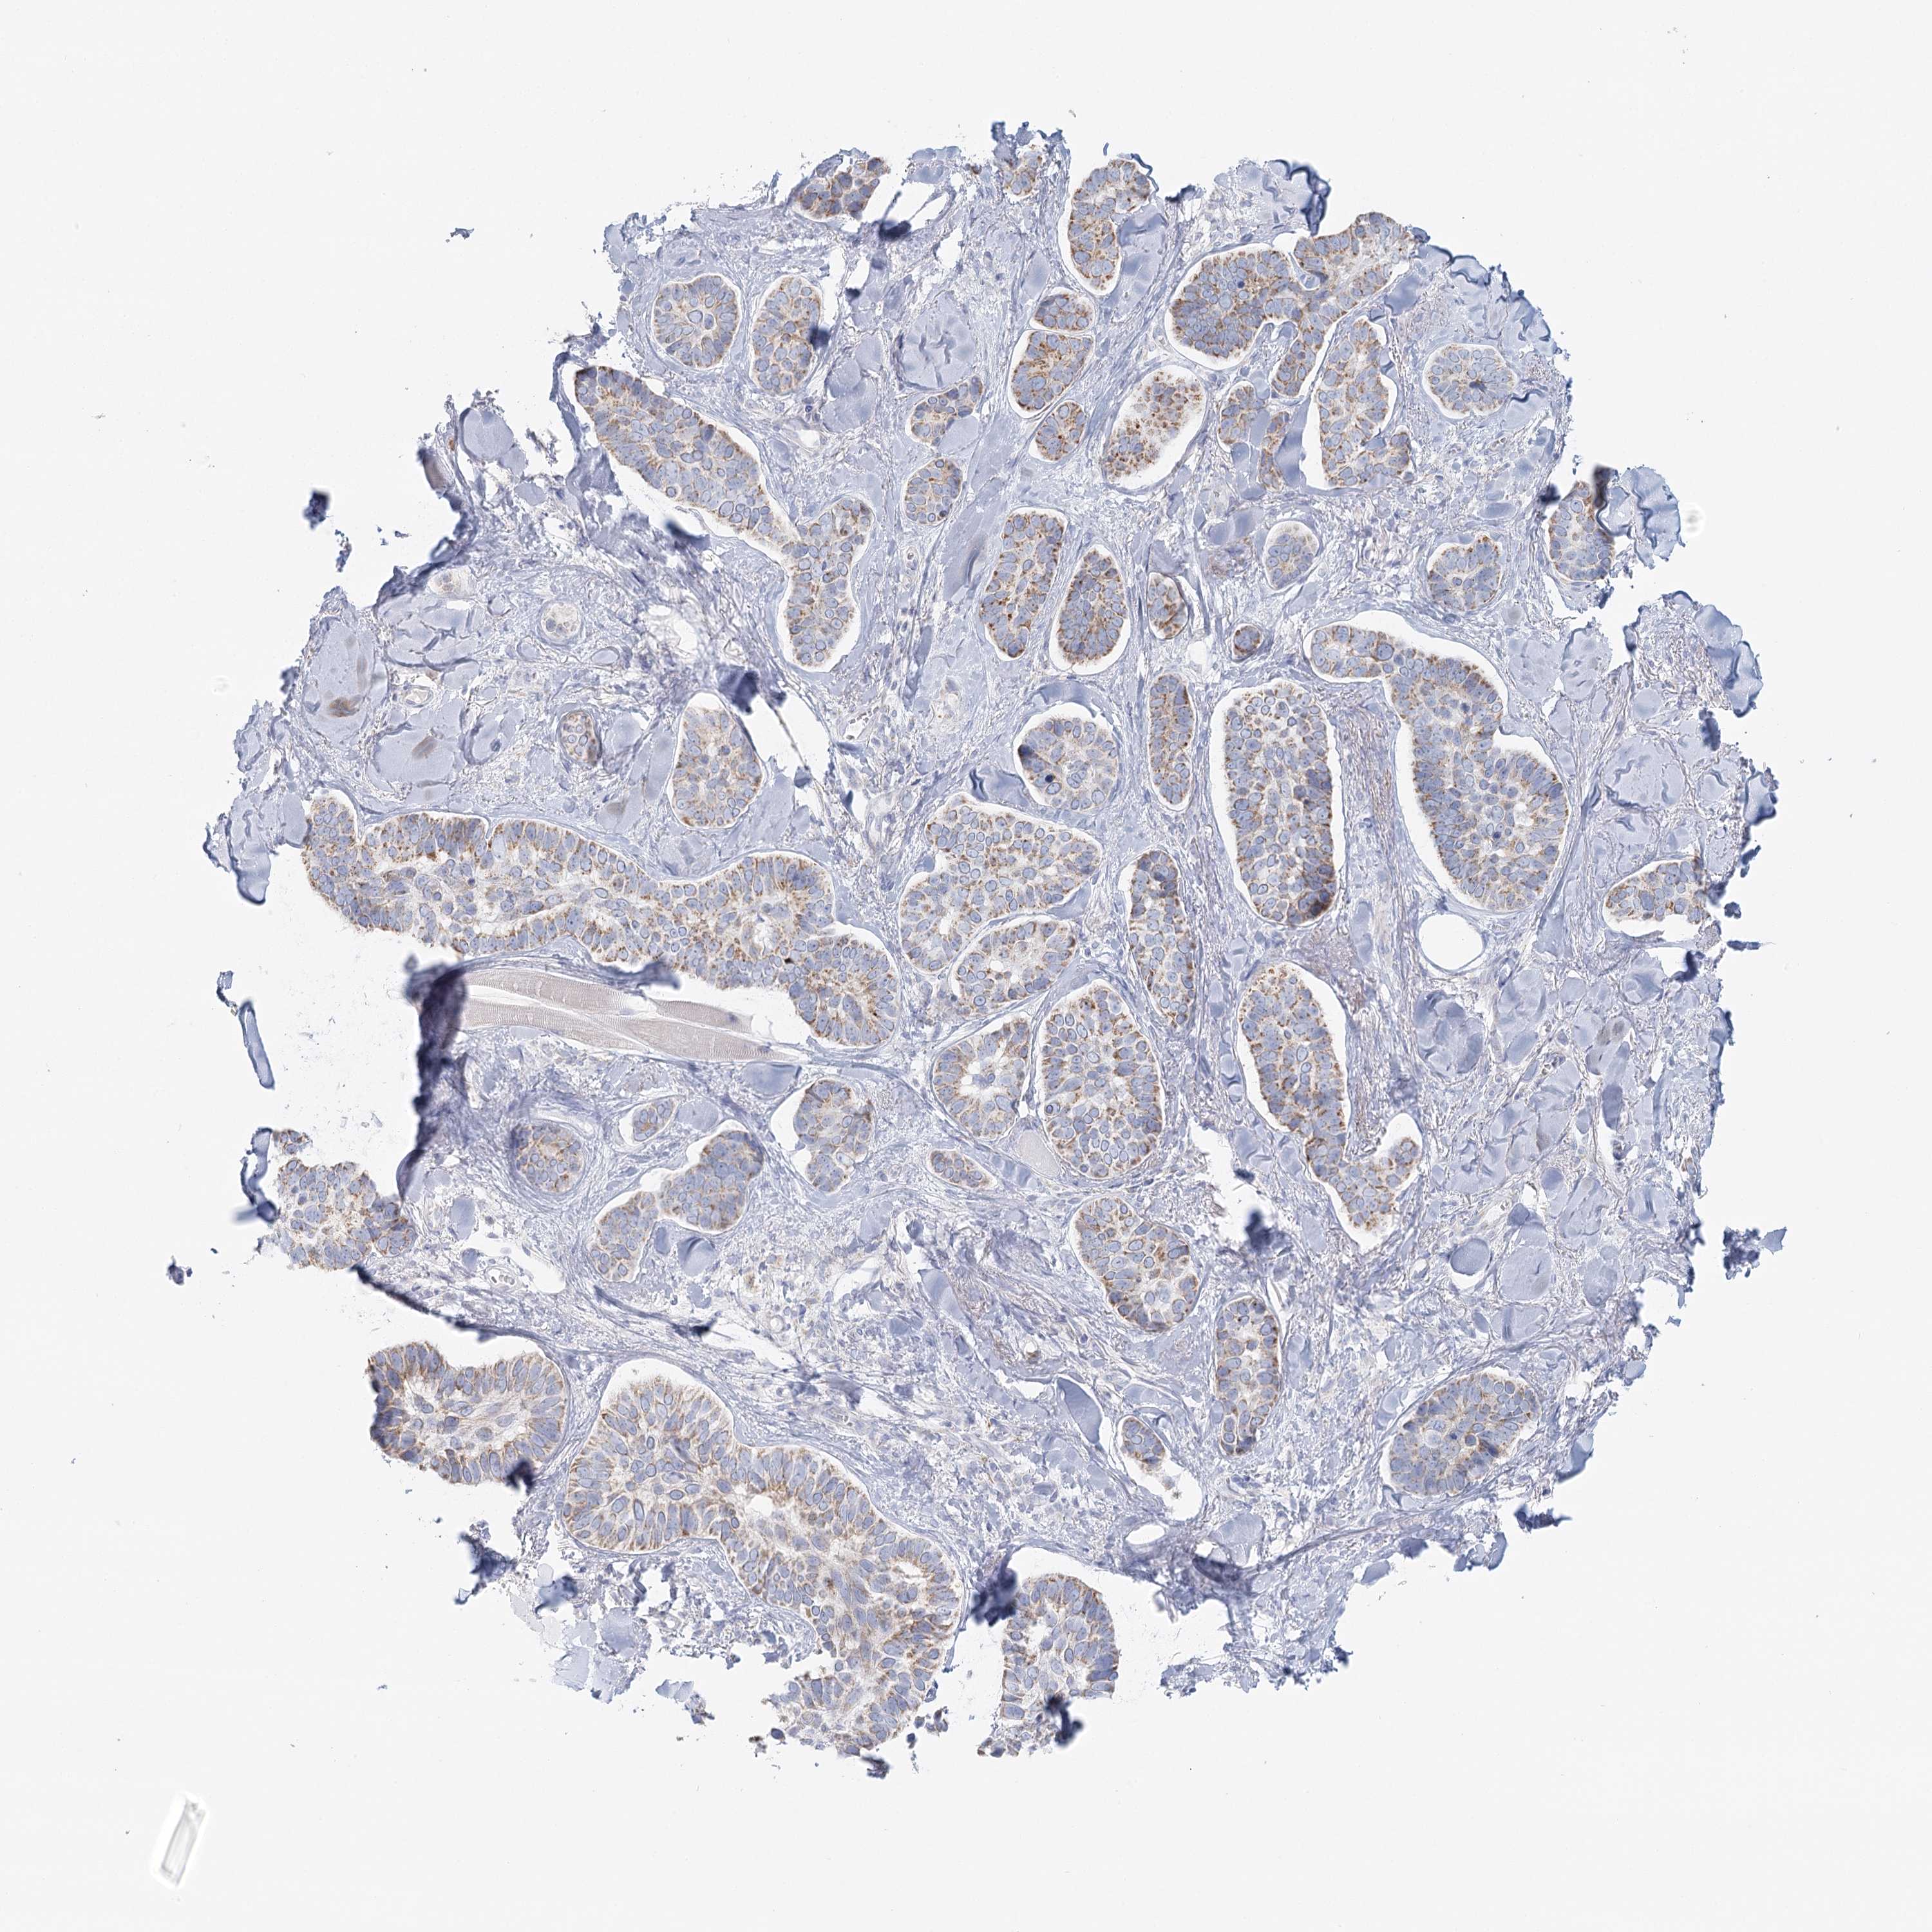

Basal cell and squamous cell cancer

SKIN CANCER - Protein expressioni

A mouse-over function shows sample information and annotation data. Click on an image to view it in a full screen mode. Samples can be filtered based on level of antibody staining by selecting one or several of the following categories: high, medium, low and not detected. The assay and annotation is described here.

Antibody stainingi

Antibody staining in the annotated cell types in the current human tissue is reported as not detected, low, medium, or high, based on conventional immunohistochemistry profiling in selected tissues. This score is based on the combination of the staining intensity and fraction of stained cells.

Each image is clickable and will lead to virtual microscopy that enables deeper exploration of all samples and also displays staining intensity scores, fraction scores and subcellular localization as well as patient and tissue information for each sample.

Antibody HPA036752

Antibody HPA036753

Staining

High

Intensity

Strong

Quantity

>75%

Location

Nuclear

Squamous cell carcinoma, NOS